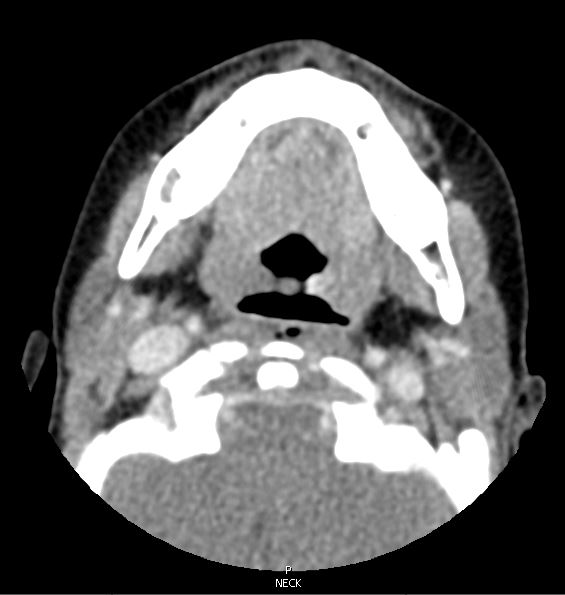

Diagnostic tests. The patient was sent for a stat soft-tissue neck radiograph, which showed air in the retropharyngeal space with thickened soft tissues, concerning for retropharyngeal abscess (Figure 1). He was sent to the emergency department, where a computed tomography scan was performed, the results of which showed a mucosal tear in the retropharyngeal soft tissues at the C2 level with associated retropharyngeal gas (Figures 2 and 3). He was admitted to the pediatric hospital for further evaluation and management.

Figures 2 and 3. Computed tomography imaging of the neck showing a mucosal tear at the C2 level with air in the retropharyngeal space.